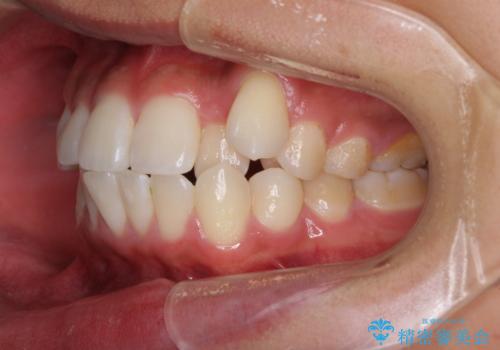

八重歯と奥歯のクロスバイト 上顎骨を拡大してインビザラインで矯正

- 八重歯を気にして来院された患者様です。

八重歯が著しいため、抜歯矯正も視野に入れて検討しましたが、臼歯の咬合関係は正常に近かったので、非抜歯矯正で進める方針としました。

上顎骨の幅が狭く、奥歯がクロスバイトとなっていたため、急速拡大装置を用いて上顎骨を側方拡大し、八重歯を収めるスペースを獲得しつつクロスバイトを改善することとしました。

上顎骨を思い通りに拡大できたため、当初の計画通りに非抜歯矯正で仕上げることができました。